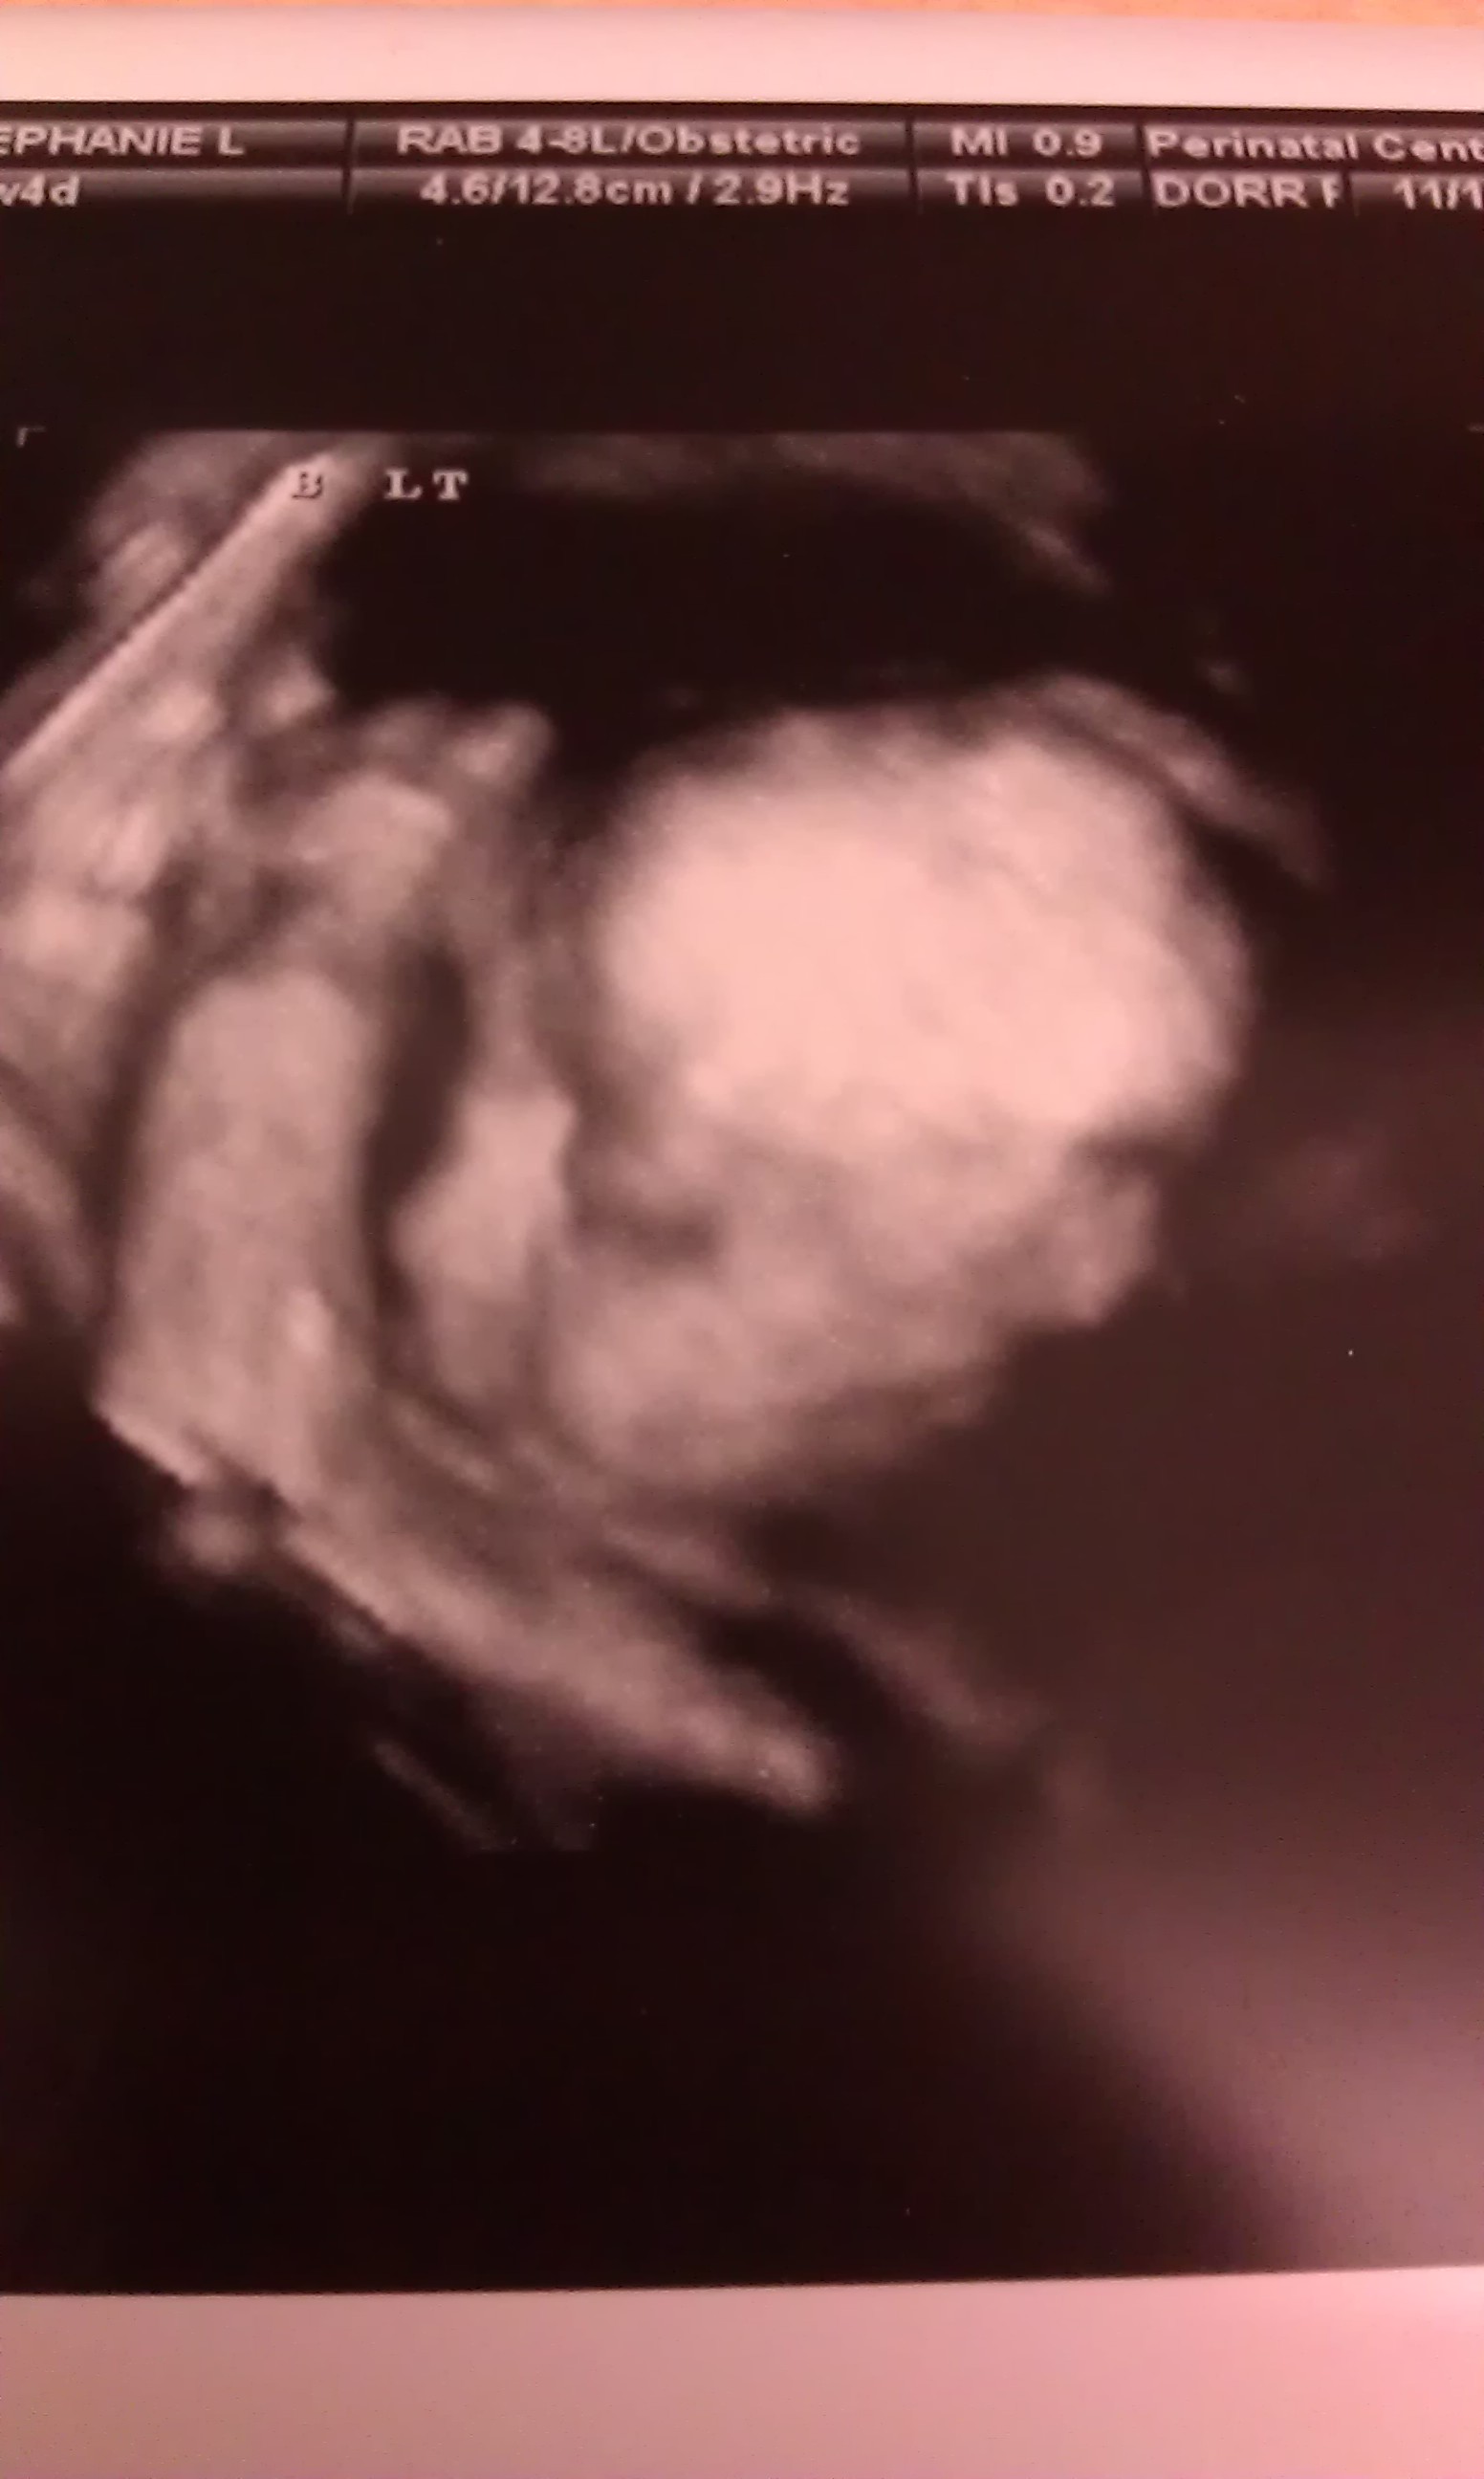

Only bad thing we found out today is babygirl is breech right now, so she better do some flippin!!!

Here's a cute pic of her we got today :)

• Great news! And sweet picture. (I'm of the UO that I love 3D u/s pics.) She has plenty of time to flip around!

I have a love/hate relationship with them lol they ARE totally creepy, but it warms my heart to see them in such detail :)